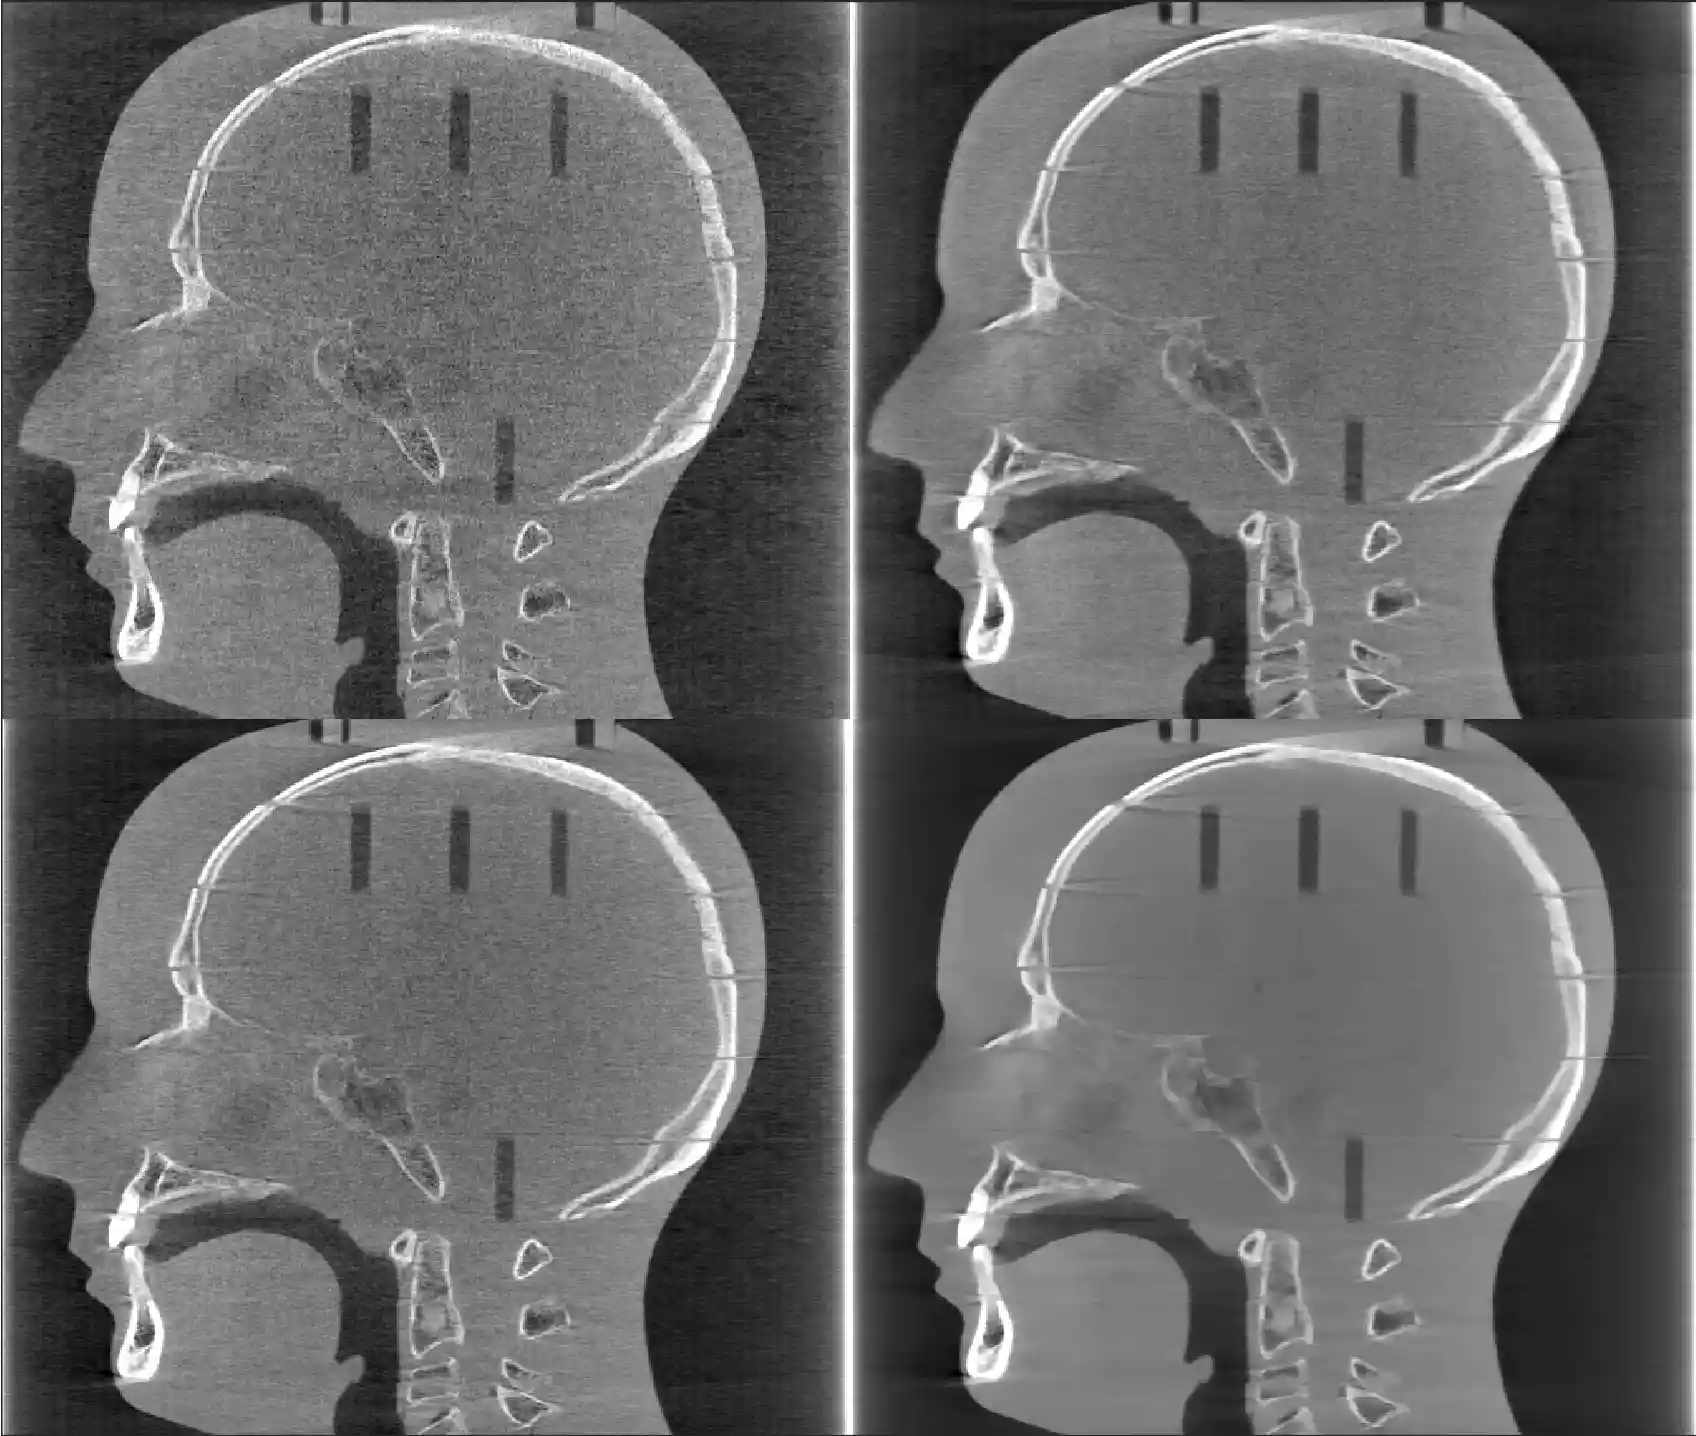

Gallery

To see a gallery of images of different CT modalities reconstructed using TIGRE click here.